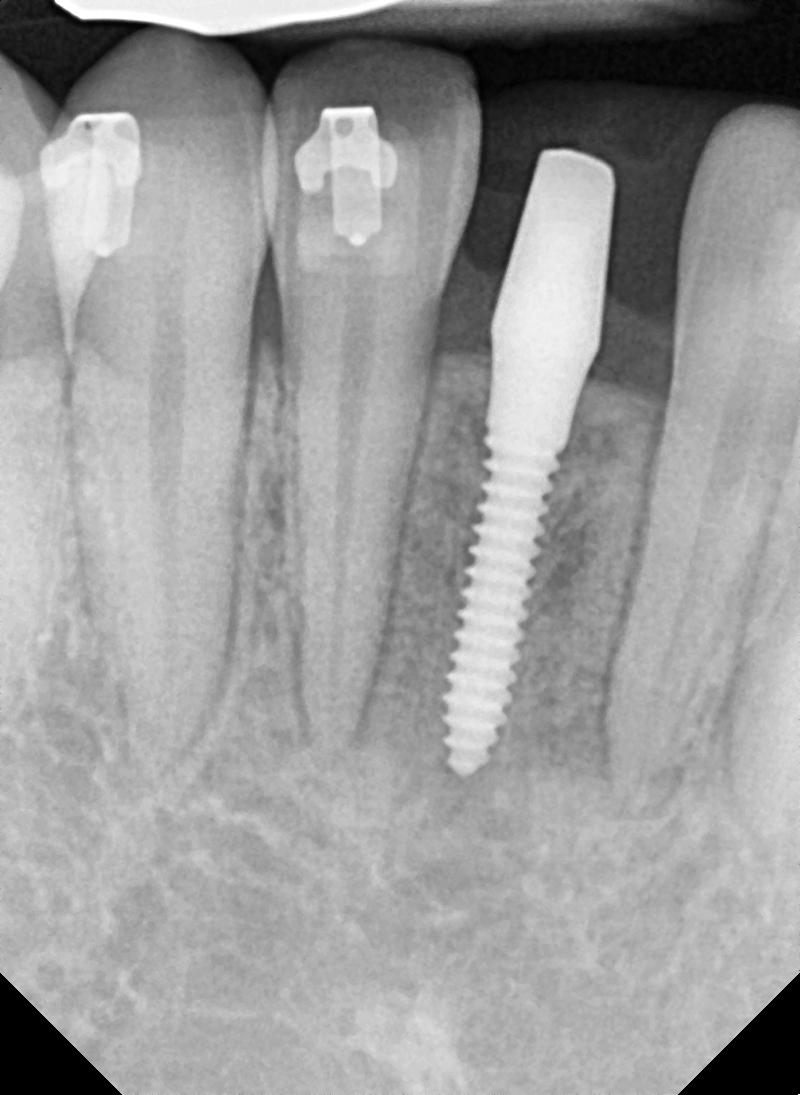

Implantation in a #41 area

Here is the case of a 24-year-old female patient.

The bone in the  #41 area where the implant is scheduled to be placed appears thin.

I had no choice but to implant 2.0mm MS. Still, some fenestration is visible. Simple bone grafting was performed on this area.This is a photo after the final prosthesis.